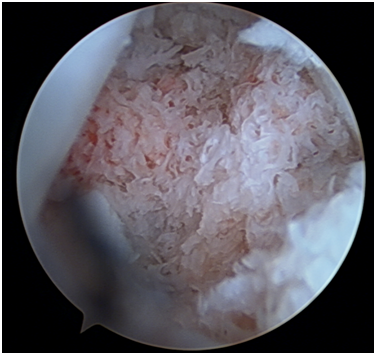

The arthroscopic procedure started with the realization of standard radio-carpic initial portals; medium-carpal portals helped with the identification of the pseudarthrosis focus (Figure 4). The pseudarthrosis focus was blown out (Figures 5 & 6). The spongious graft of the contralateral iliac crest was harvested. Placement of the graft through the midcarpal portal of visualization by adapting the arthroscopy trocar (Figures 7-9). The traction was withdrawn. The graft was fixated with a percutaneous anterior approach and arthroscopic support and placement of the double compression screw with radiographic support (Figure 10).

Figure 9 Arthroscopic view of the graft.